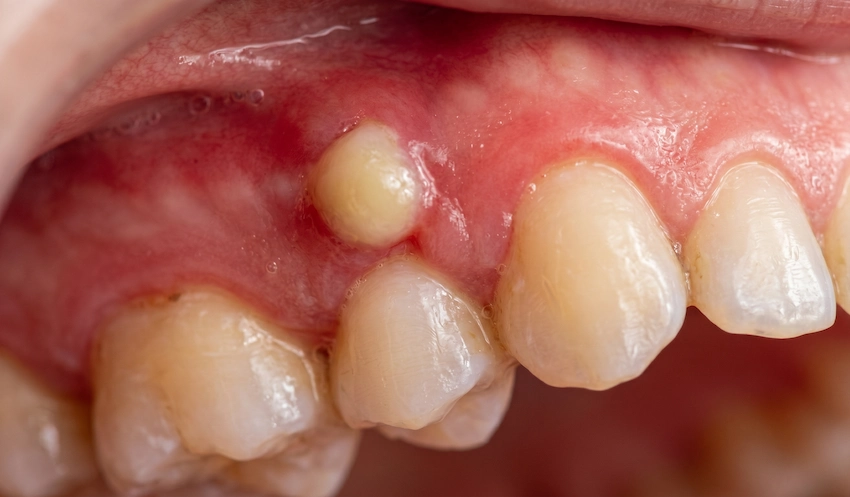

Une douleur forte et constante pourrait être ce qui vous empêche de dormir la nuit. Une petite bosse peut soudainement apparaître sur vos gencives. Un abcès douloureux de la gencive est un problème difficile à tolérer ; il ne faut pas l’ignorer car c’est un signe d’avertissement de votre corps. Donc, si vous avez un abcès de la gencive, c’est comme un autocuiseur enterré sous votre sourire. C’est une petite zone remplie de pus, résultant d’une infection bactérienne. La pression et la douleur s’intensifient, et en l’ignorant, c’est comme laisser la fondation d’une maison exposée à l’eau – finalement, l’os qui soutient les dents est détruit.

Professeur Docteur Coşkun Yıldız indique que les patients prennent presque toujours une infection de niveau superficiel pour une infection interne. Les abcès parodontaux se développent principalement dans la zone entre la dent et la gencive, et résultent principalement d’une infection de la gencive. La bactérie est produite, et la nourriture piège la gencive, qui devient alors hypertrophiée. D’un autre côté, les abcès périapicaux proviennent de l’intérieur de la dent – généralement une dent cariée ou endommagée – et traversent la racine jusqu’à l’os et la gencive qui l’entourent.